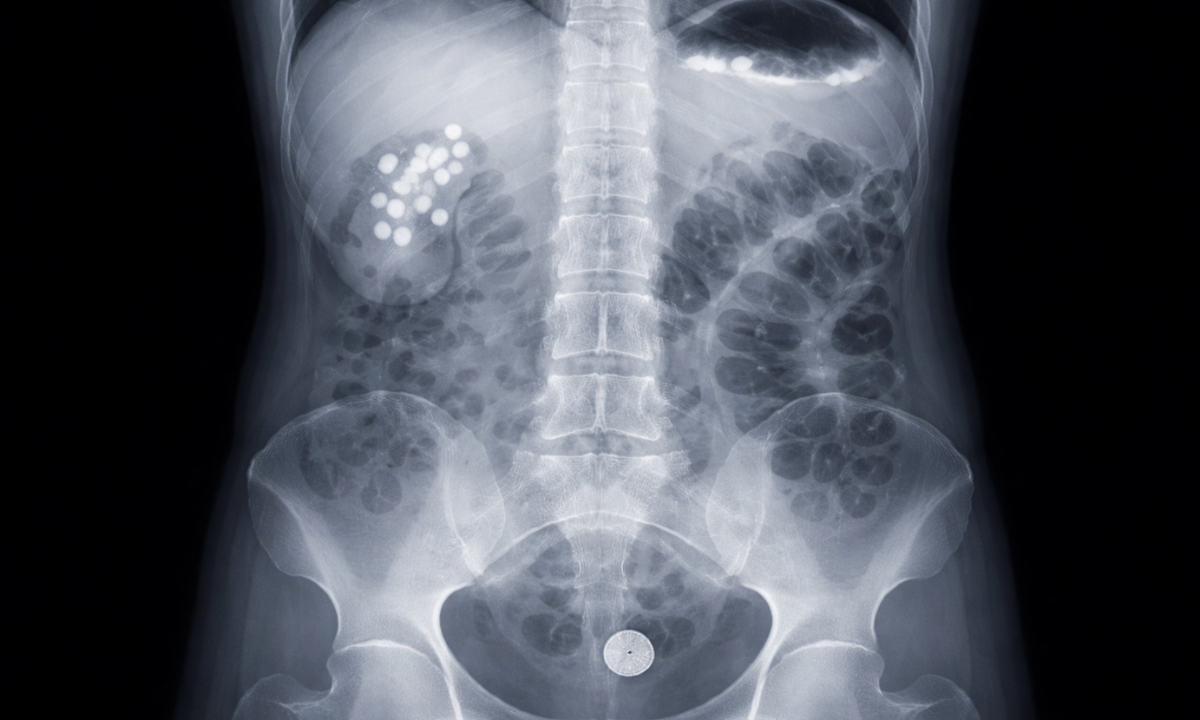

Abdominal Radiography

An X-ray of the abdomen, often called a KUB (Kidney, Ureter, Bladder) scan, is frequently used to diagnose digestive and urinary tract issues.

- Kidney Stones: Many stones are calcium-based and show up clearly as white spots.

- Blockages: It can reveal intestinal obstructions or the presence of swallowed foreign objects.

- Perforation: It detects free air in the abdominal cavity, which is a medical emergency indicating a hole in the stomach or intestine.